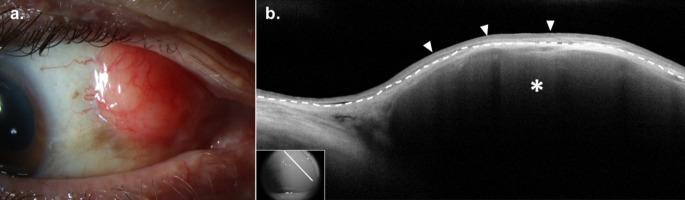

Purpose of review: Subepithelial lesions of the ocular surface represent a diverse group of pathologies which may be difficult to diagnose clinically. Some of these lesions are relatively uncommon, may result in systemic manifestations, or occur secondary to systemic disease. The purpose of this review is to summarize current approaches to the diagnosis and management of six subepithelial conjunctival lesions.

Recent findings: The standard for the diagnosis of subconjunctival lesions remains histopathologic evaluation; however, high-resolution anterior segment optical coherence tomography (HR-OCT) is a useful supplemental diagnostic tool that may facilitate diagnosis. Recent advancements in the management of subconjunctival lesions include targeted systemic therapies in conjunctival melanoma and ultra-low dose radiation radiotherapy in conjunctival lymphoma.

Summary: The development of HR-OCT has provided clinicians with valuable supplemental diagnostic information to guide the diagnosis of subepithelial lesions. Additionally, novel treatment modalities may provide an alternative to traditional surgical interventions in some pathologies.